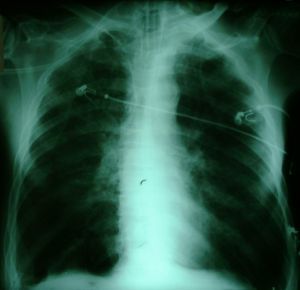

The above X-rays illustrate one of the most dramatic and successful

maneuvers you can perform in Intensive Care. The patient whose X-rays

are shown is a man in his sixties who had surgery for malignancy,

and subsequent to multiple complications including a deep vein

thrombosis, pulmonary embolism, and perineal sepsis, developed hypoxaemia

and bilateral pulmonary infiltrates, in the absence of clinical evidence of

elevated left atrial pressure. A recruitment maneuver produced

substantial improvement in his oxygenation, which was maintained.

By 23:00 on the same day he was weaned down to an FiO2 of

35% with the following blood gas:

pH=7.39 pCO2=35 pO2=69 Saturation 94

The above patient was selected as an example of a mild to moderate

success. In many cases, recruitment is even more dramatic (We felt

that if we showed you such cases, you wouldn't believe us)!

Note that as we are at an altitude of about 1600 metres, the

pCO2 in our patient is lower than one would regard as normal at

sea level. (Patients at our altitude tend to chronically hyperventilate

slightly).